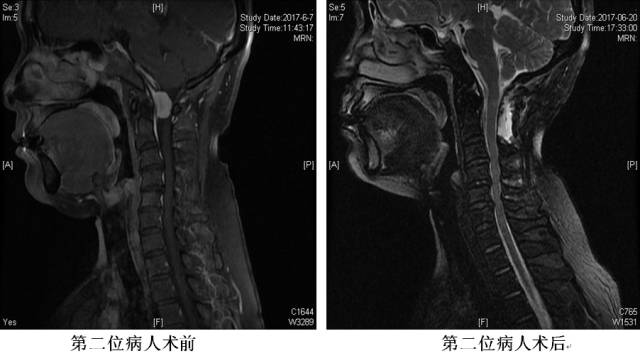

脊柱外科跨越手术禁区

枕颈交界硬膜内肿瘤由于位置特殊,位于脑干延髓和脊髓的交界,周围有双侧的椎动脉以及颅底神经和C1-2脊神经分支,以往多为手术治疗的禁区。

近日,青大附院脊柱外科市南病区收治2例此类患者,皆因肿瘤体积大、位置特殊、风险高等原因多家求治未果,慕名求诊于青大附院。脊柱外科充分多次会诊,充分准备,成功将肿瘤完整切除。术中患者生命体征平稳,术后1周康复出院,恢复良好。